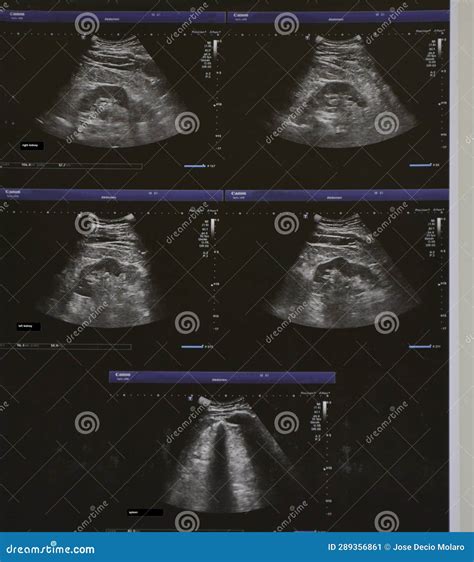

*Bazo Y Riñon Ecografia*, also known as spleen and kidney ultrasound, is a non-invasive diagnostic procedure that uses high-frequency sound waves to create images of the spleen and kidneys. This imaging technique helps healthcare providers assess the structure and function of these vital organs, aiding in the diagnosis and monitoring of various medical conditions.

• Image Generation: The sound waves are converted into electrical signals, which are then processed by a computer to create real-time images of the spleen and kidneys.

• Review and Analysis: The radiologist or sonographer reviews the images to assess the size, shape, and condition of the spleen and kidneys. Any abnormalities or areas of concern are noted for further evaluation.

The results of *Bazo Y Riñon Ecografia* are interpreted by a radiologist, who will review the images and provide a detailed report. The report will include information about the size, shape, and condition of the spleen and kidneys, as well as any abnormalities or areas of concern. The healthcare provider will then discuss the findings with the patient and develop an appropriate treatment plan.